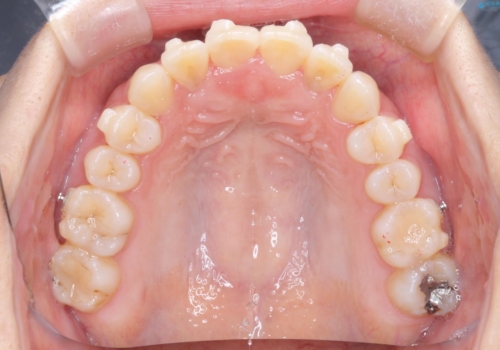

【インビザライン】前歯の凸凹をなおしたい

- 前歯の凸凹を主訴に来院されました。

上顎の急速拡大を行なったのちインビザラインにて治療を行なっております。

今回のケースは後戻りのリスクを低くし、またディスキング量を減らすために上顎の急速拡大を行なっております。